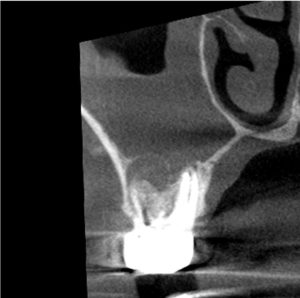

今回歯の上部は健全な部分がたくさん残っているので、上から直径3ミリほどの小さな穴を開けそこから、根の内部の吸収部を除去しようと試みました。

すると吸収部にはただ単に歯が溶けているのではなく、肉芽という歯茎の一部が入り込んでしまっているので、穴を開けた瞬間に血が噴き出してきて、血まみれで中を見るのが困難な状態でした。

そこで肉芽を様々な器具や技で除去をし、出血を止め薬剤で消毒しました。

言葉で書くのは簡単ですが、これには非常に時間がかかりとても困難な治療でした。そこにMTAセメントを用い、根の先端の方(赤矢印)と吸収部(黄色矢印)を同時に埋めました。

黄色矢印の左の方を見ていただくとわかると思いますが、外にはみ出しているのがわかるかと思います。

これはMTAセメントを押し込んで、わざとはみ出しています。